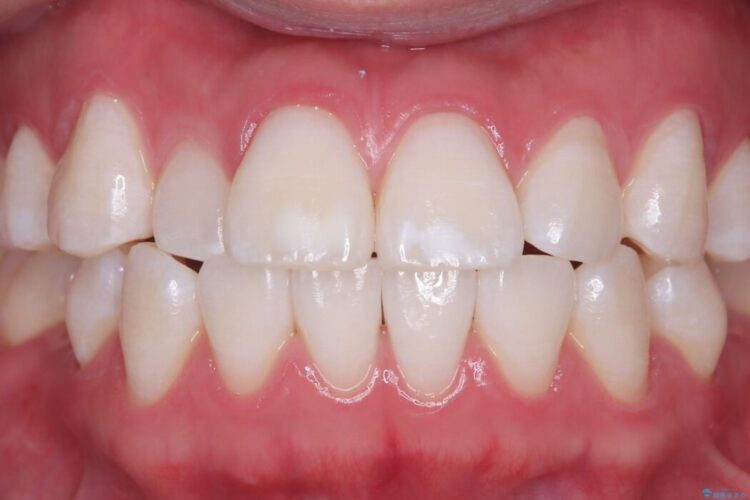

長期的な安定性を重視したセラミック治療

歯と歯の間に虫歯があった患者様です。

治療期間(治療回数):1ヶ月(2~5回) | 概算治療費:13.2万円(税込)(仮歯:10,000円+オールセラミッククラウン 3年保証110,000円)